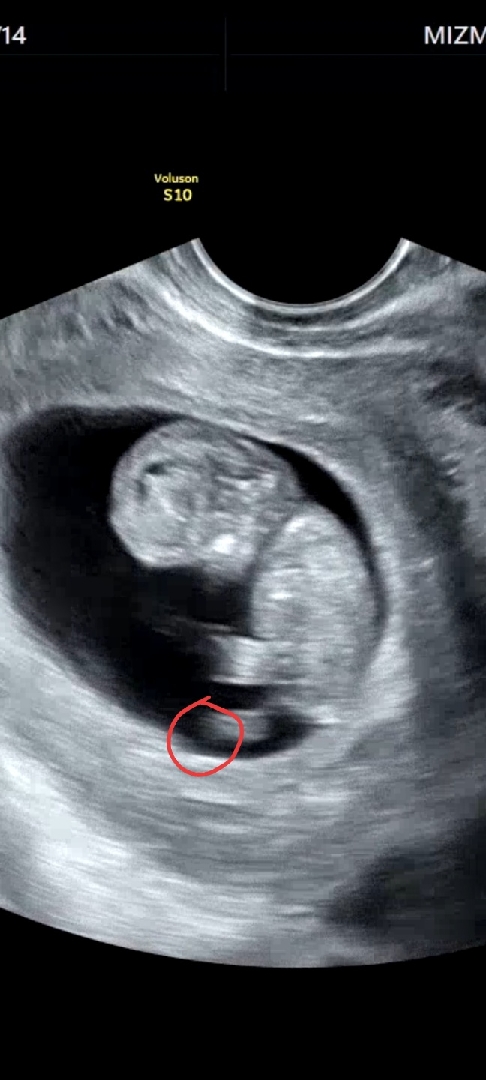

10주3일차 발가락이 맞는건가요?

발가락이 맞는거 같기도 하고? 아닌거 같기도 하고? 동영상 캡쳐한건데 손가락도 희미하게 보이는거 같았는데 캡쳐가 힘들더라고요~ 3.66cm에 180bpm 아기는 주수에 맞게 건강한거 같아요 :)

저건 그냥 흔들린 것 같은데요.. 정밀초음파 찍을 때도 각도 맞춰서 자세히 봐야 볼 수 있는데 저 시기에 저 초음파로 알 수는 없어요